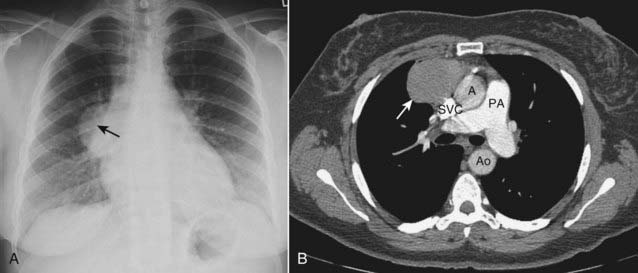

image

Figure 12-3 CT of a substernal thyroid goiter without and with contrast enhancement.

These are two images at the same level in a patient who was scanned both before (A) and then after intravenous contrast administration (B). A, On CT scans, substernal thyroid masses (solid white arrow) are contiguous with the thyroid gland, frequently contain calcification (dotted white arrow) and (B) avidly take up intravenous contrast but with a mottled, inhomogeneous appearance (solid white arrow). This mass is displacing the trachea (T) slightly to the left.